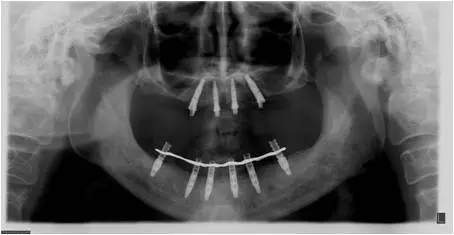

10個(gè)月后出現(xiàn)左上頜咬合痛,X線檢查發(fā)現(xiàn)上頜左側(cè)前磨牙區(qū)傾斜種植體周圍低密度影,臨床檢查種植體松動(dòng),其余種植體骨結(jié)合良好,遂拔除該種植體(圖3-4)。愈合3個(gè)月,CBCT片顯示:25區(qū)種植窩空虛(圖5),愈合不佳,26區(qū)竇底剩余骨高度不足2mm(圖6),其余種植體骨愈合良好,15區(qū)傾斜種植體邊緣骨疑似吸收至第三螺紋(結(jié)合全景片)?;颊咭蠊潭ㄐ迯?fù)。

圖3

圖4